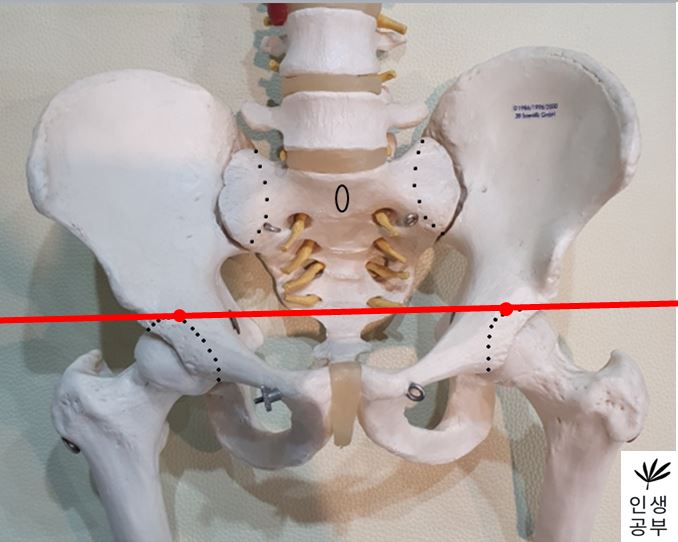

2) 대퇴골두(Femoral head) 최상단에 양쪽에 각각 한개씩 점을 찍어줍니다.

3) 두 점을 연결하는 선을 긋습니다. 이 선의 이름은 대퇴골두선(FHL : Femur Head Line)이라고 합니다.

6) 1번째나 2번째 엉치뼈 결절(sacral tubercle) 정가운데 찍은 점에서 대퇴골두선(FHL : Femur Head Line)을 기준으로 수직인 선을 긋습니다.

선을 그었을 때 점이 있는 쪽 골반이 IN이 됐다는 뜻이고, 없는 쪽은 EX 되었다는 뜻입니다.